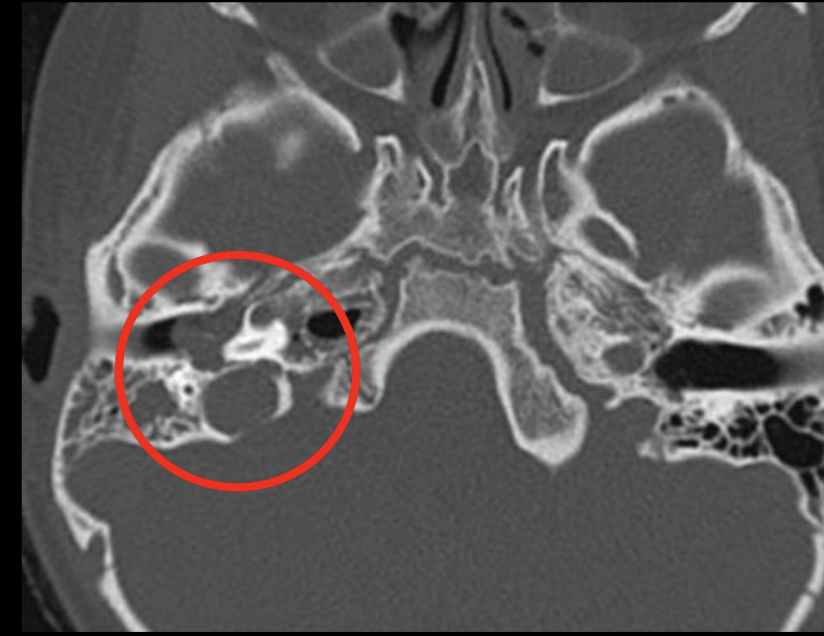

10

Q

Diagnóstico

A

Otitis media

¿Qué esperamos encontrar en una TC de otitis media?

Masa bien definida en oído medio y erosiones osiculares (de los huesesillos)